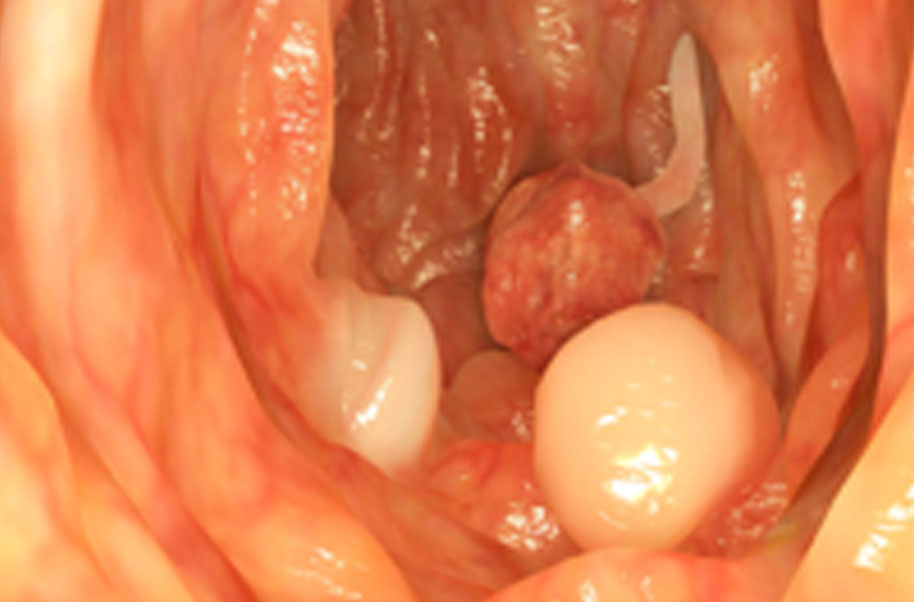

Adenomatous Polyps

Colon cancer also known as bowel cancer , colorectal cancer (crc), is the development of cancer from the colon or rectum (parts of the large intestine). A cancer is the abnormal growth of cells that have the ability to invade or spread to other parts of the body.